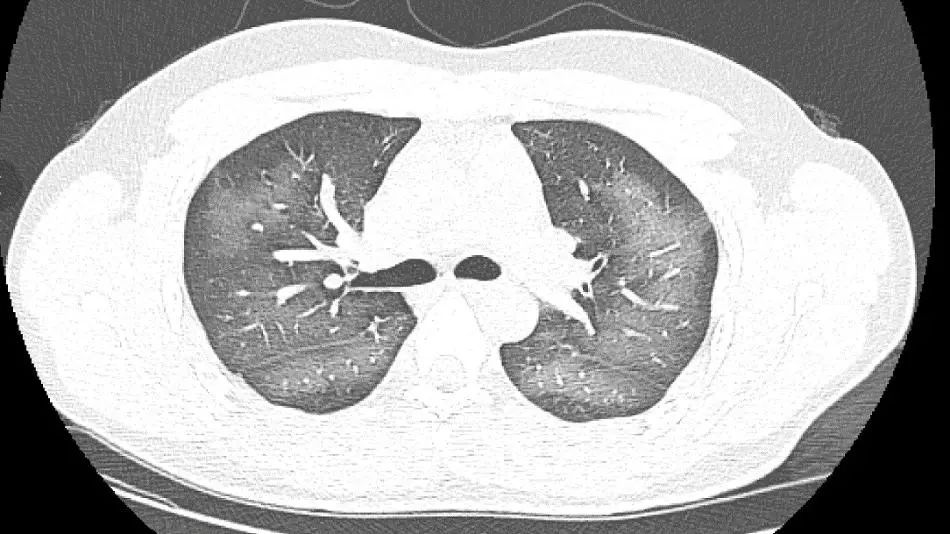

长沙市第三医院近期收治了一位用防晒喷雾后肺部变白的年轻患者。据介绍,这位患者外出前使用了防晒喷雾,在对着面部喷洒时一不小心误吸,随即出现胸闷、咳嗽的症状。症状一直持续到第二天仍未好转,他才急忙来到医院就诊。

完善相关检查后,这位患者的肺部CT让医生们大吃一惊:双肺赫然呈现大范围白色样病变,报告提示“白肺”。

医生介绍,“白肺”一般是指重症肺炎在X线或CT检查下的表现,患者肺部呈现一大片的白色状态。“白肺”患者往往会出现呼吸困难、呼吸衰竭,严重者还会出现其它脏器功能障碍。

医生表示,除了感染、弥漫性肺泡出血综合征等“白肺”最常见的病因外,吸入有害物质如粉尘、喷雾等,也可导致肺部出现大范围白色样病变。这位年轻的患者就是因为使用不当,吸入了一部分防晒产品进入肺部,导致“白肺”的发生。